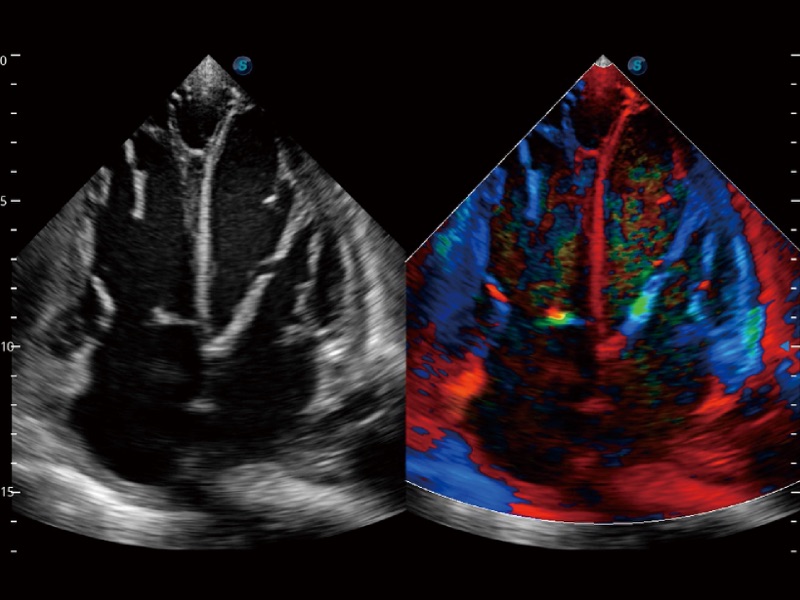

• SR Flow 高分辨率血流成像技术

高分辨率血流成像技术提高了对低速血流信号的检测能力。在提高空间分辨率的同时,也克服了血流外溢现象,为用户提供更加真实的血流动力学信息。

• 心血管应用

临床图